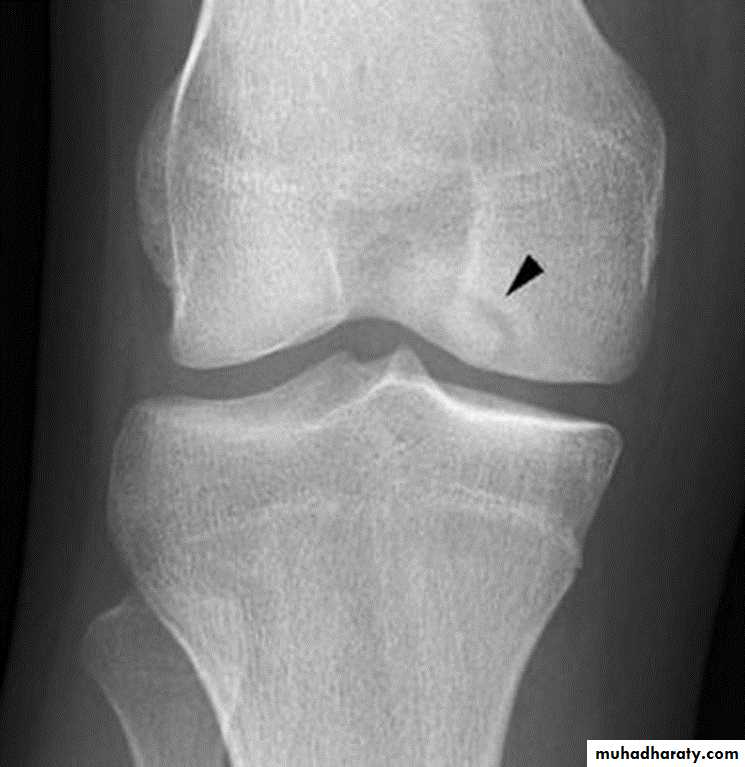

Osteochondritis of

lumbar vertebral bodies (advanced case).Osteochondritis dissecans

affects the large articular surface , commomnly medial femural condylee ,talus and trochlea .Ends by separation of the affected part in to the joint space resulting in intra-articular loose body .

Osteochondritis dissecans of the medial femoral condyle Osteochondritis dissecans of the medial part of the articular surface